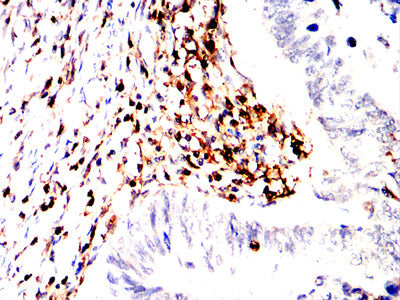

分类: 科研抗体货号: 32361别名: CT132; SPAS1; spergen1应用: IHC反应种属: Human